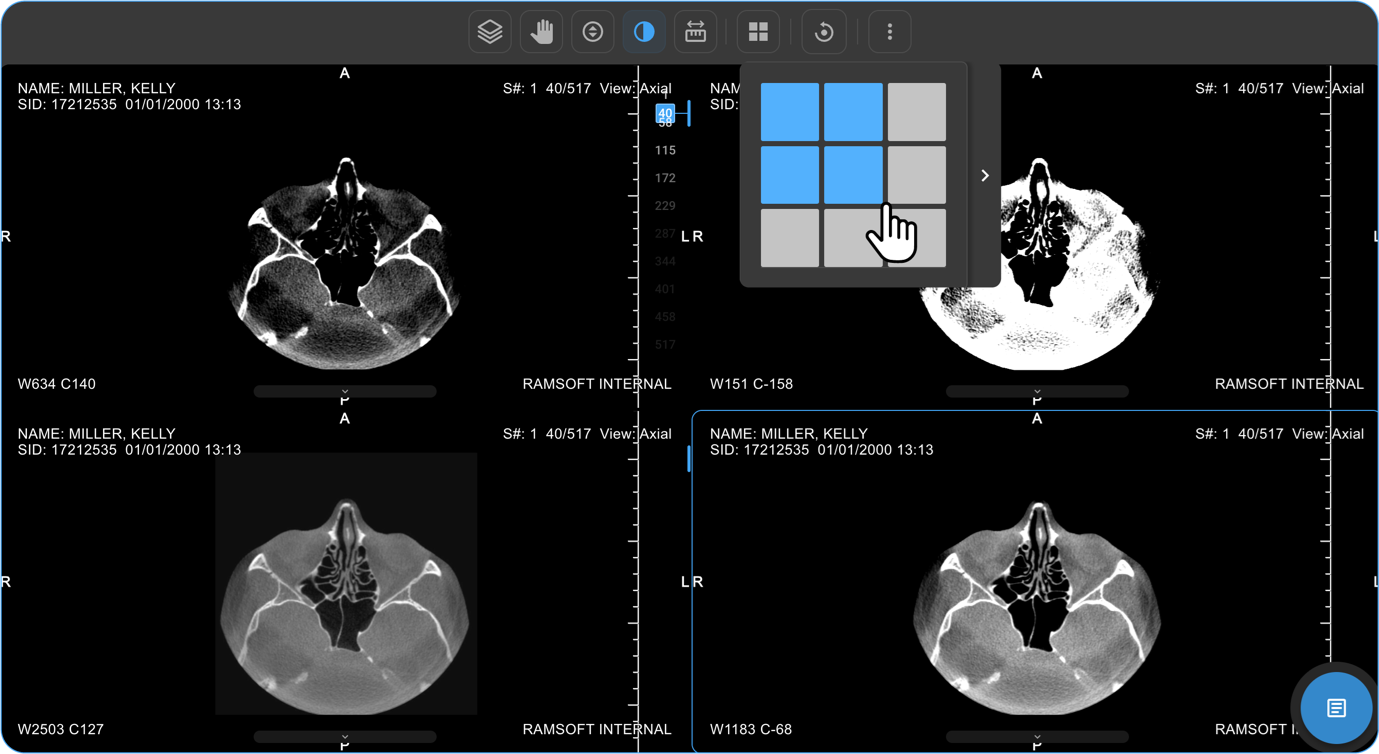

How Do I Change the Viewport Layout?

-

Open Layout Selector from the toolbar.

a. A 3×3 grid appears, with the current layout highlighted.

Adjust Viewports:

a. Drag to increase/decrease viewports (up to 8×8 grid per monitor).

Apply Hanging Protocols:

a. Available in a drawer beside the selector.

Select one to apply it:

a. Single Monitor: Affects only that monitor.

b. Multi-Monitor: Applies to all monitors.

How Do I View Multiple Images or Series in Different Layouts?

- If there are multiple images or a series of images, you can customise the display layout to enhance your viewing experience.

- Locate and click on the Change Layout icon in the image viewer toolbar at the top of the screen.

- Select the desired layout format to switch between a single-frame view and a multi-frame display for comparing multiple images simultaneously.